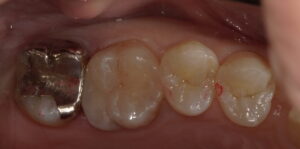

実際の症例はこんな感じです。

20代男性。検診希望で来院されました。上顎左側第一大臼歯遠心がなんとなく黒ずんでいます。

レントゲン撮影を行ったところ、大きな虫歯が出てきました。

赤い部分が虫歯です。

虫歯を全てとりきったところです。神経ギリギリまで進行していました(゜o゜)

レジン充填を行いました。